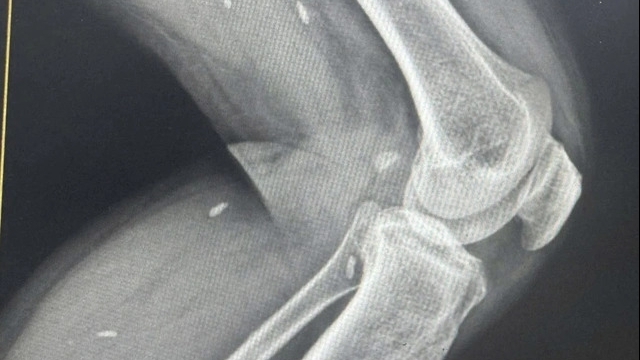

![]() |

| Phim chụp của bệnh nhân. Ảnh: Bệnh viện E |